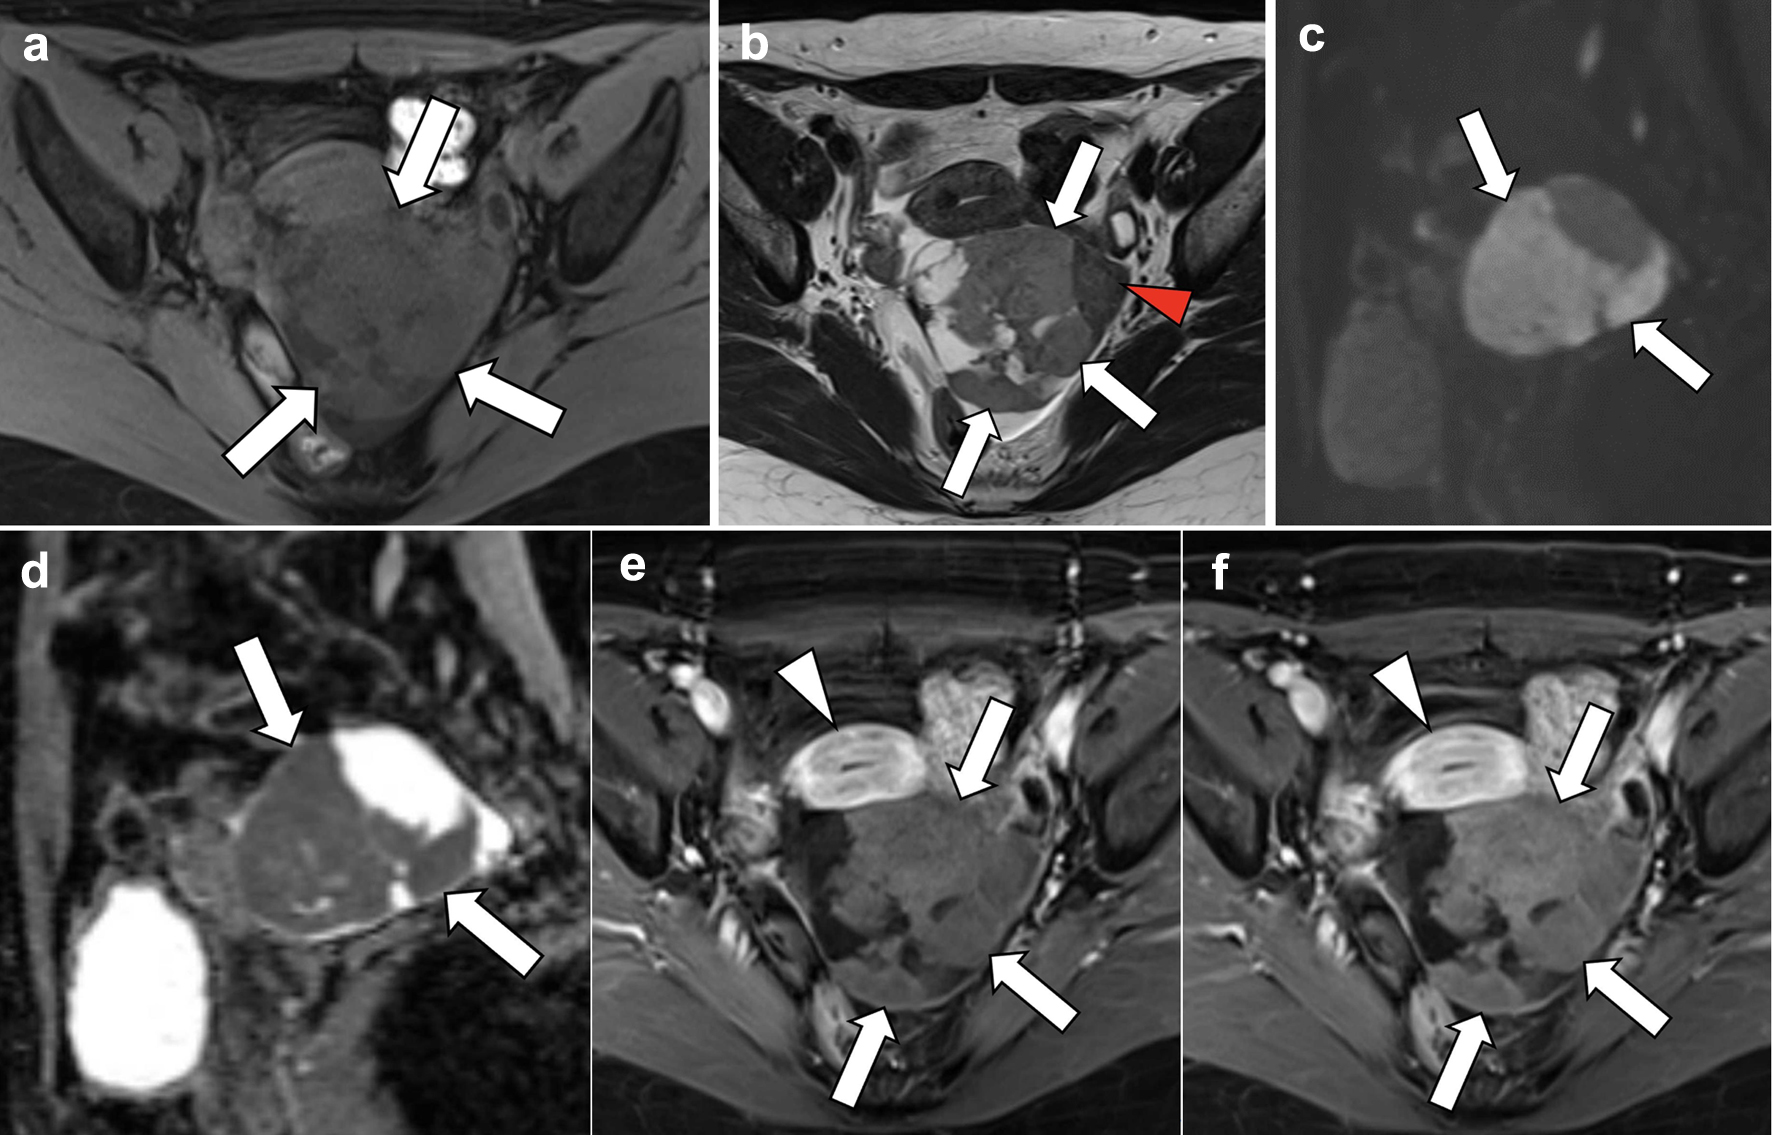

A 60-year-old postmenopausal woman, gravida 2 para 1, was found to have a pelvic mass during a medical check-up. The patient had no symptoms or relevant medical history. There was no significant family history reported. The patient was referred to the Department of Obstetrics and Gynecology of our hospital wherein ultrasonography was performed. It revealed an echogenic mass with smooth, well-defined borders in the left adnexal area. Posterior acoustic shadowing was also observed. The mass exhibited hypo-vascularization on color Doppler study (Fig. 1). The right ovary appeared normal with minimal ascites present. Serum levels of tumor markers, such as CA19-9, CA125, and carcinoembryonic antigen (CEA), were within normal ranges while the serum level of estradiol (E2) was 16 pg/mL (normal range: < 39 pg/mL). Subsequent computed tomography (CT) revealed an 8 cm cystic and solid mass in the left ovary (Fig. 2). MRI of the lower abdomen was performed using a 3T MAGNETOM Skyra (Siemens Healthineers, Erlangen, Germany). The left ovarian solid mass with cystic components was well circumscribed and isointense compared with the skeletal muscle on T1-weighted imaging (T1WI) (Fig. 3a). On T2-weighted imaging (T2WI), the mass comprised a mildly hyperintense solid portion on the right side, which included several cystic components, and a smaller, hypointense, solid portion on the left side (Fig. 3b). On DWI with a b-value of 800 s/mm2, the larger solid portion on the right side of the mass showed hyperintensity. However, hypointensity was observed on the apparent diffusion coefficient (ADC) map. The left solid portion of the mass showed an absence of restriction (Fig. 3c, d). On DCE-MRI, compared with pre-contrast T1WI, the entire solid portion excluding cystic components of the mass showed a faint and gradual enhancement pattern, whereas the uterine myometrium showed relatively strong enhancement (Fig. 3e, f).

![]() Click for large image | Figure 3. Magnetic resonance imaging. (a) T1-weighted axial section, (b) T2-weighted axial section, (c, d) diffusion-weighted sagittal images, and (e, f) dynamic contrast-enhanced axial images. On T2-weighted imaging, the left ovarian mass is mildly hyperintense in the larger right solid portion (b; arrows), with several cystic areas detected, and hypointense in the smaller left solid portion (arrowhead). On diffusion-weighted imaging, reduced diffusion is observed in the solid portion of the mass (c, d; arrows), which is pathologically proven to be a cellular fibroma component with hypercellularity. On dynamic contrast-enhanced imaging, compared with pre-contrast T1WI, the entire solid portion excluding cystic components of the mass shows a faint and gradual enhancement pattern (e, f; arrows), corresponding to a tumor with abundant fibrous components pathologically proven, whereas the uterine myometrium shows relatively strong enhancement (arrowheads). |

In the present case, the mass was isointense compared with the skeletal muscle on T1WI; while on T2WI, the right solid portion of the mass, constituting the majority of the tumor, was mildly hyperintense and the left solid portion was hypointense (Fig. 3a, b). On DWI, the right solid portion showed hyperintensity, which was pathologically proven to be a cellular fibroma component with hypercellularity (Figs. 3c, 5a). In contrast, the left solid portion, which showed an absence of restriction, was proven to be a regular fibroma component (Figs. 3c, 5b). DWI generally reflects the cellular density of a lesion. Thus, the current DWI findings are consistent with the result of the histological examination that most areas of the mass showed hypercellularity and some areas of normal density were mixed.

Kitajima et al reported that ovarian fibromas typically exhibit a low signal intensity on T2WI and weak enhancement with contrast material [1]. In the present case, the smaller left solid portion of the mass exhibited low signal intensity on T2WI while the diffusion-restricted solid portion on the right side of the mass exhibited a weak enhancement. The entire solid portion of the mass, regardless of the area, showed a faint and gradual enhancement pattern on DCE-MRI, suggesting a tumor with abundant fibrous components. Torsion of the current affected ovary was identified during surgery. The torsed ovary is characterized by disrupted blood flow, which is seen as abnormal enhancement after intravenous contrast agent administration. Heterogeneous minimal or absent enhancement indicates the evolution of ovarian torsion from ischemia to infarction [6]. However, the torsion of approximately one rotation was without necrotic appearance without observing pathological findings of necrosis or infarction. Thus, in this case, torsion might be considered to have little effect on the contrast effect of the tumor. Based on these findings, without those from DWI, the tumor of the present case could have been presumed to be a fibrous tumor containing ordinary fibroma components, thus highlighting the difficulty in distinguishing between benign and malignant tumors.